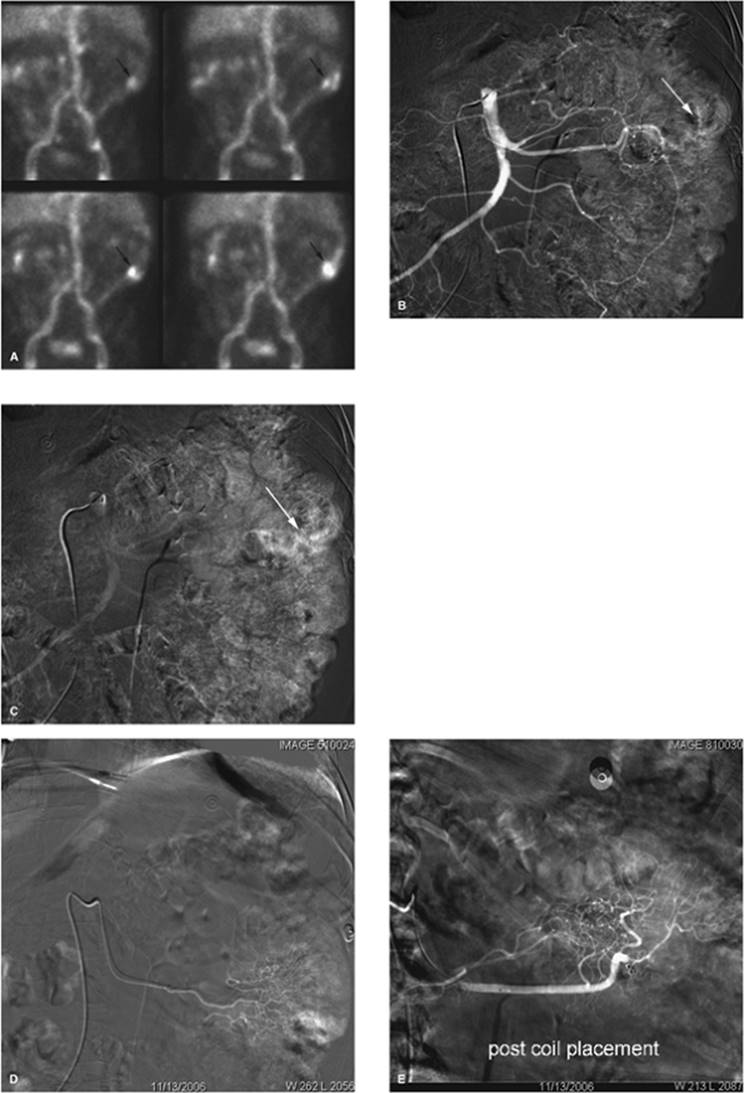

Empyema

Drainage of an empyema can frequently be performed at the bedside under ultrasound guidance, with the patient's position dependent on his or her ability to assist and the exact location of the collection; a sitting position is often preferred. The collection is localized, entry site marked, site prepped, local anesthesia obtained, and dermatotomy performed followed by deep blunt dissection. A 14 to 20 French catheter is then inserted, often with the trocar technique. The empyema is aspirated and the catheter connected to Pleur-Evac water seal pleural drainage system. The overall success rate for percutaneous drainage of empyema is 77% (6) (Fig. 35.5A–D).

Figure 35.4. CT-guided drainage of infrahepatic abscess. A: CT scan through the fluid collection (asterisk) with localizer grid applied on the skin over the target. B: Following determination of pathway, entry site marking, sterile skin prep and drape, and local anesthesia the access needle is advanced under CT guidance into the fluid collection. Repeat CT is performed to evaluate needle path and depth (arrow). C: Postdrainage obtained at the same level as A shows loop of drainage catheter (short arrow) in markedly decompressed abscess cavity. (Case courtesy of Lauren Alexander, MD, Gainesville, FL.)

Thick fluid collections may require the use of intrapleural thrombolytic injection such as t-PA, to disrupt fibrin septae. This can be accomplished with an infusion of rt-PA solution containing 2 to 6 mg of rt-PA in 50 to 250 mL of normal saline. This is infused daily for 1 to 3 days. There does not appear to be any significant systemic effect associated with this intralesional infusion of the thrombolytic medication, and there is an approximate 94% clinical improvement rate (7).

Figure 35.5. A 19-year-old patient with sepsis and cough. A: Axial CT at the level of the midchest demonstrates an 8.5-cm fluid collection in the right posterior hemithorax (asterisk) with compression atelectasis of the adjacent lung. Direct percutaneous access is blocked due to inferior margin of the scapula, overlying ribs, and aerated lung. B: Patient was placed in a left-side-down decubitus position. Change in position provides direct posterior access to the fluid collection. A localizer grid has been placed to mark site of access. C: Access gained with micropuncture needle system and then a 14 Fr drain placed over a wire. Fluid aspirated with syringe and then drain was secured in place and connected to suction bulb. D: Postdrain placement CT. (Case courtesy of Lauren Alexander, MD, Gainesville, FL.)